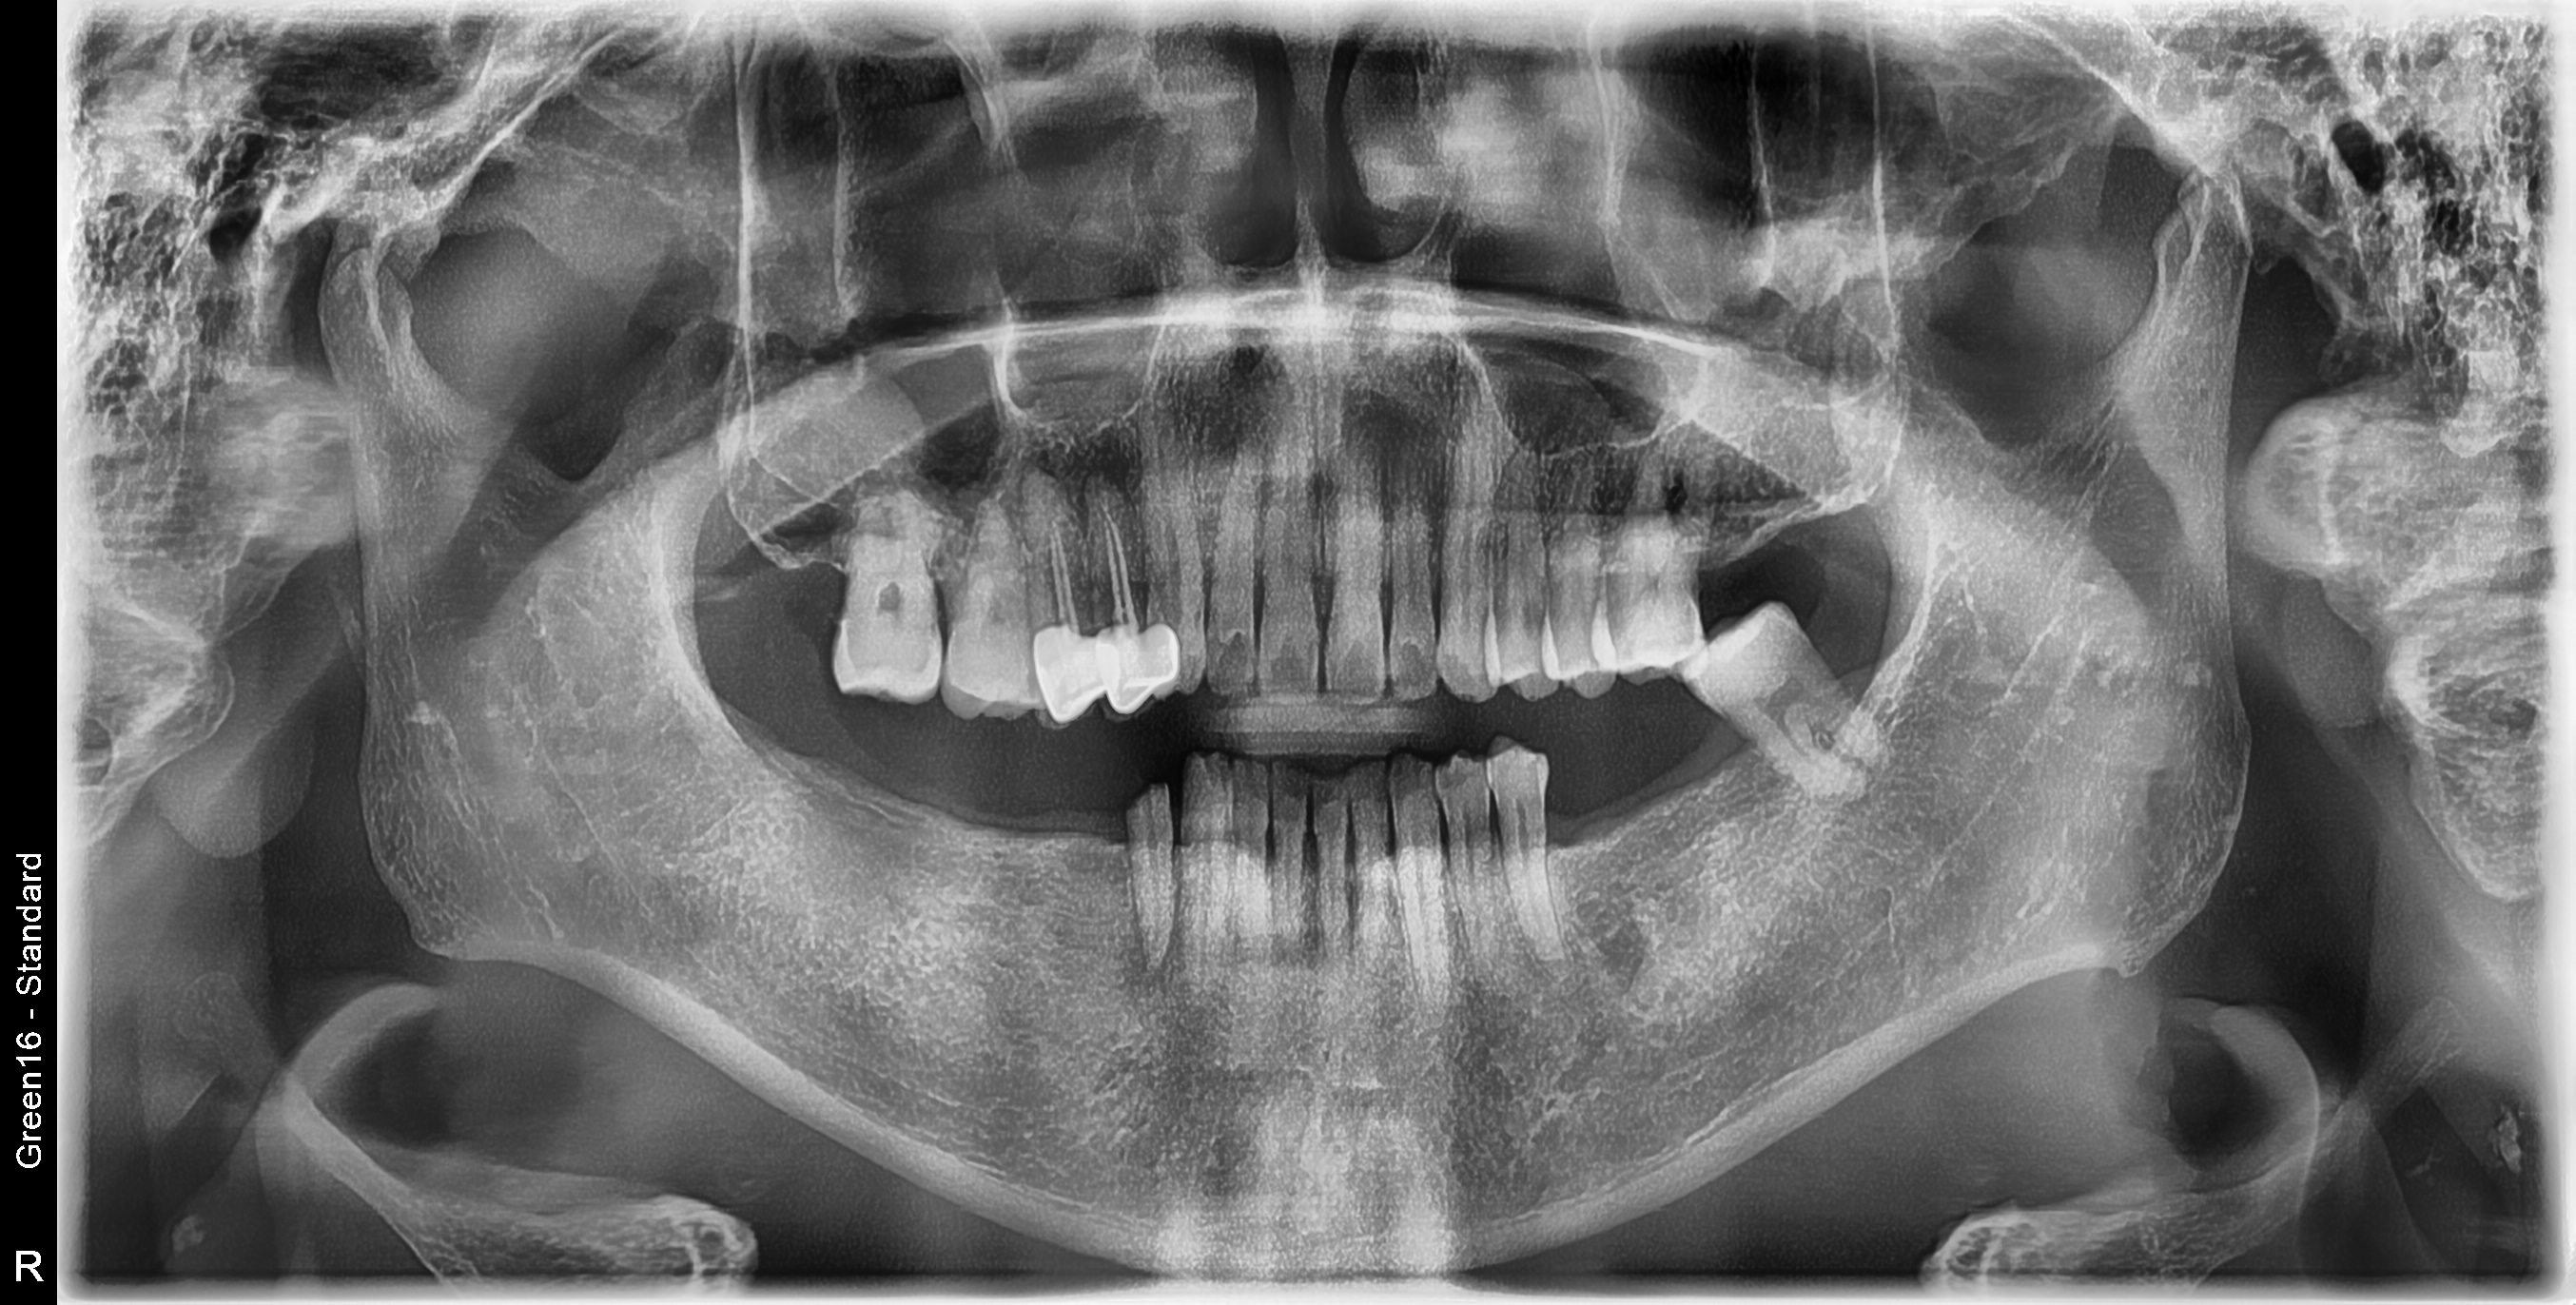

수술 전

수술 후

하악 구치부 식립사례

전후사진